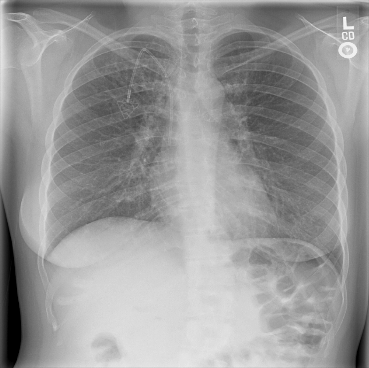

The data used in the following experiments consists of DICOM X-ray images, obtained from the University of Washington Medical Center and affiliated institutions, centered in Seattle by scanning radiology reports from the last three years. Inclusion criteria were: (i) Digital Radiography (DR) images, (ii) Chest radiographs, (iii) Posterior-anterior or anterior-posterior view position, (iv) Adult patients. Any personal health information was removed. Image-level labels were derived from natural-language processing based analysis of the reports. Cases were partially reviewed by a radiologist to confirm appropriate finding in the report’s impression section and this represented a critical finding. The resulting dataset contained 1003 images: 437 with pneumothorax, 566 with a different or no abnormality detected. We generated pixel-level annotations of the pneumothorax region for 305 of the positive cases. For training and evaluation, we divided the dataset into five cross-validation splits of similar size, such that images of the same patient resided in the same split.